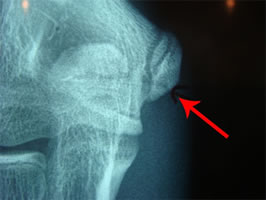

エコーでは上記の像(↑)です。

わかりにくいかもしれませんが、右肘矢印の先に骨皮質の不連続像が確認できます。噛み砕きますと、白い線(骨の表面)が途切れています。画像上ではチョットだけ途切れている様にしか映っていませんが、少しでも途切れていればいわゆる骨折タイプの可能性が高くなります。